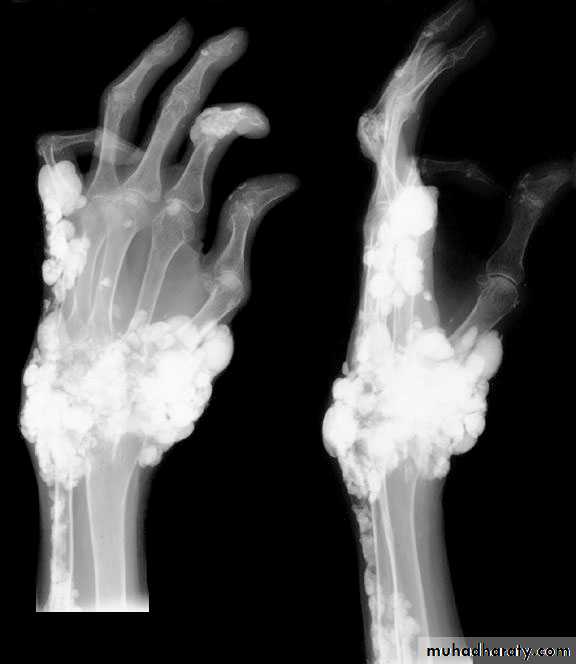

Hyperparathyroid bone disease:Now rare due to early diagnosis and treatment

Caused by prolonged sustained effect of PTH on bone, resulting in increased osteoclastic activity and extensive bone remodeling with associated osteoblastic activity and fibrous tissue repair (osteitis fibrosa).

The patient may present with bone pain and tenderness, fracture and deformity.

Primary hyperparathyroidism(Radiological features)

Characteristic changes on plane X ray are:

Demineralization, subperiosteal erosion and resorption of terminal phalanges

Soft tissue calcification affecting arterial walls, hands or cornea

Chondrocalcinosis